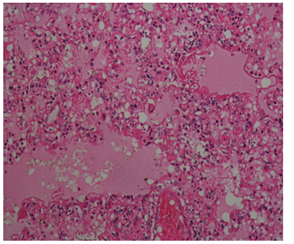

In the histopathological examination report obtained after the autopsy performed in the Morgue Department of Adana Forensic Medicine Group Presidency; ‘Edema, atelectasis, hyaline membranes, haemosiderin-loaded macrophages in large areas in the lungs, acute respiratory distress syndrome compatible appearance (Figure 1). Liver, kidney, spleen, heart, thymus, brain, brain stem and cerebellum congestion are detected and it is stated that the death of the person has an acute respiratory insufficiency syndrome resulting in anaphylactic reaction result related to insect bite. In our case; history, investigation information and histopathological examination were taken into account when ARDS was diagnosed.

Figure 1 Edema, atelectasis, hyaline membranes, haemosiderin-loaded macrophages in large areas in the lungs, acute respiratory distress syndrome (HEX100, HEX200, HEX400).